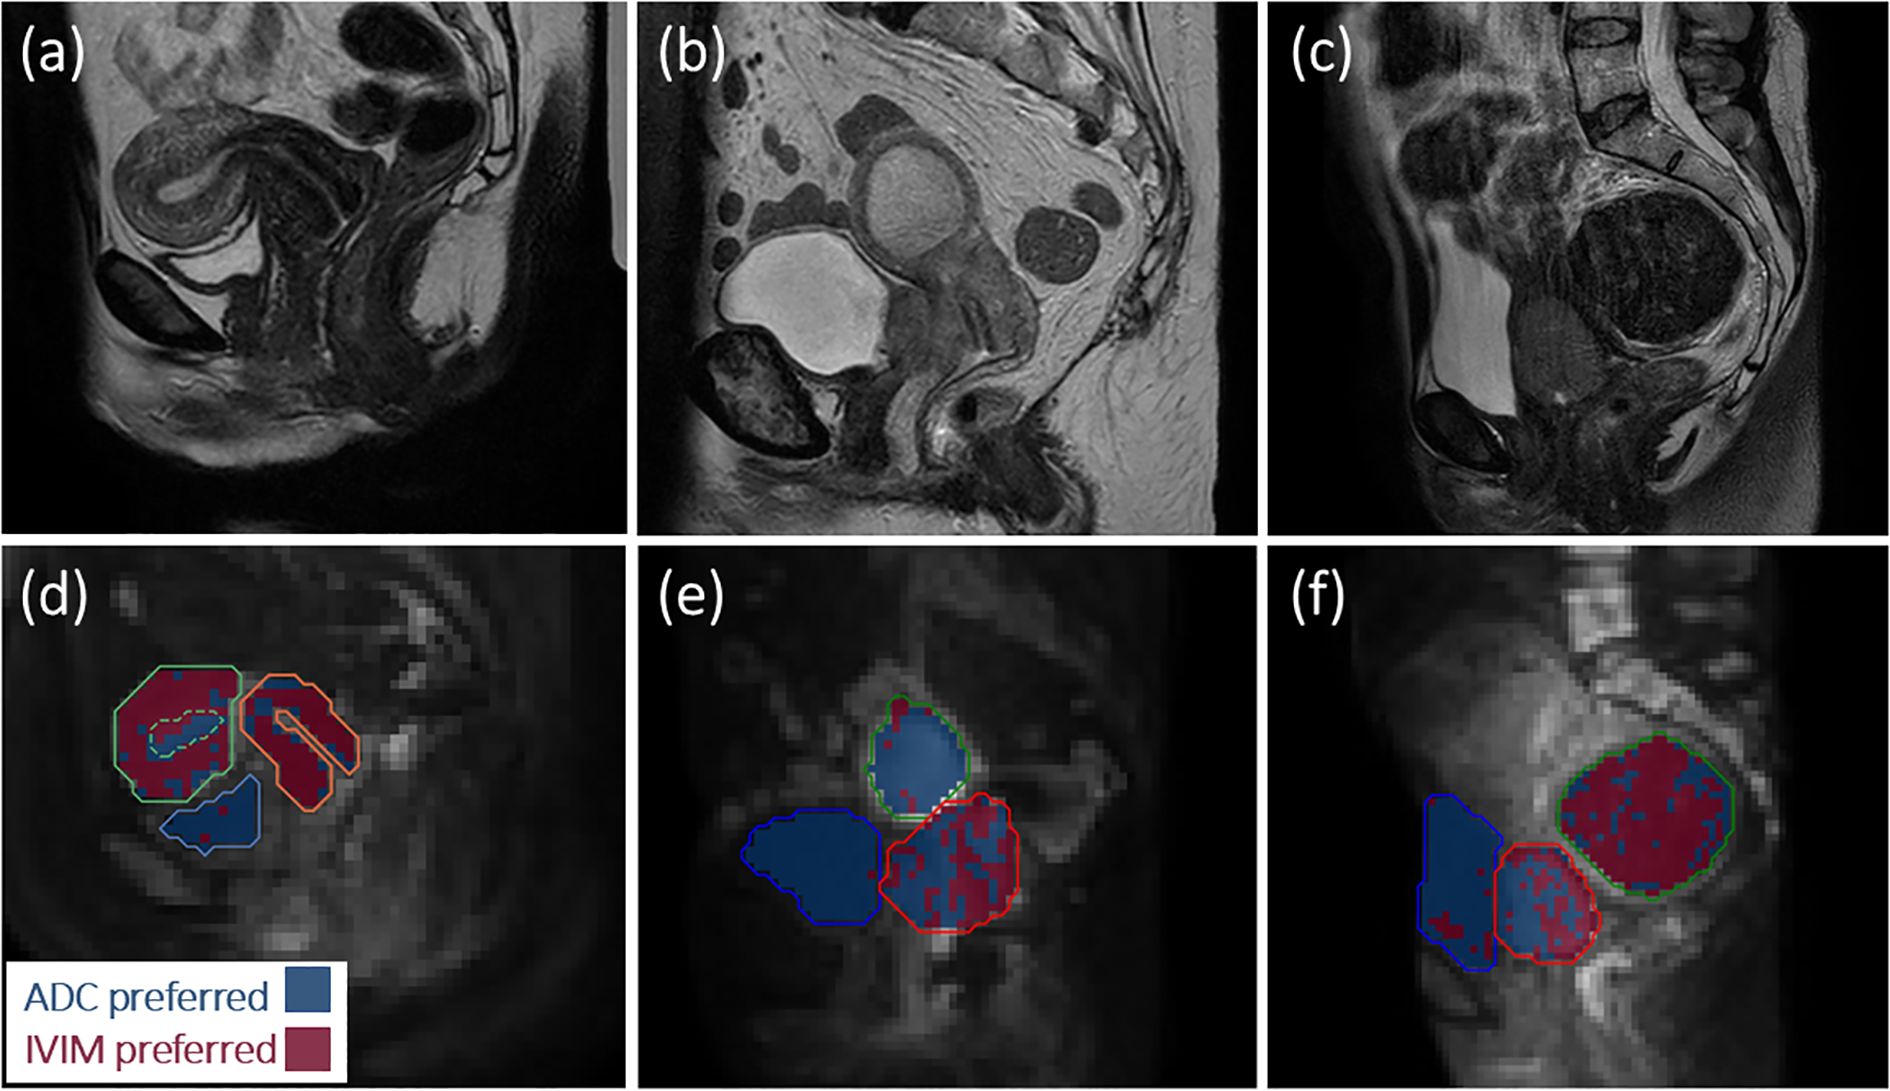

Intra-voxel incoherent motion (IVIM) biomarkers require validation for translation into clinical practice. This work evaluates repeatability and sensitivity to treatment of IVIM biomarkers in the uterine cervix, and assesses suitability of the IVIM model. Six healthy volunteers underwent two scans to evaluate repeatability. Eight patients with stage IIB-IVA cervical squamous cell carcinoma were scanned pre-treatment, and at weeks 3 and 5 into treatment. IVIM and apparent diffusion coefficient (ADC) model fits were compared using the corrected Akaike information criterion (AICc). Tissue diffusion coefficient, D, perfusion signal fraction, f, and pIVIM, the fraction of voxels better described by the IVIM model, were measured. ADCs calculated with minimum b-values of 0 (ADCb0) and 150 s/mm2 (ADCb150) were compared with f to assess sensitivity to perfusion. Model preference maps qualitatively reflected physiological characteristics of different tissues. Healthy cervix within-subject coefficients of variation were 8% (D), 15% (f), and 12% (pIVIM). Tumour D increased from baseline to week 3 (p=0.02). Baseline pIVIM showed large inter-patient variability (range: 0.13-0.68), which persisted throughout treatment. The difference between ADCb0 and ADCb150 correlated with f (repeated measures correlation coefficient r=0.76, p=0.002). IVIM biomarkers are repeatable in healthy cervix tissue. Tumour D is sensitive to early therapy-induced changes. The IVIM model is not favoured in all tumour voxels, indicating the presence of heterogeneous tumour microenvironments. ADC calculated using b=0 s/mm2 can be influenced by a perfusion-dependent bias. Not all tumour voxels are best described by the IVIM model. ADC in cervical tumours can suffer from perfusion-dependent bias.